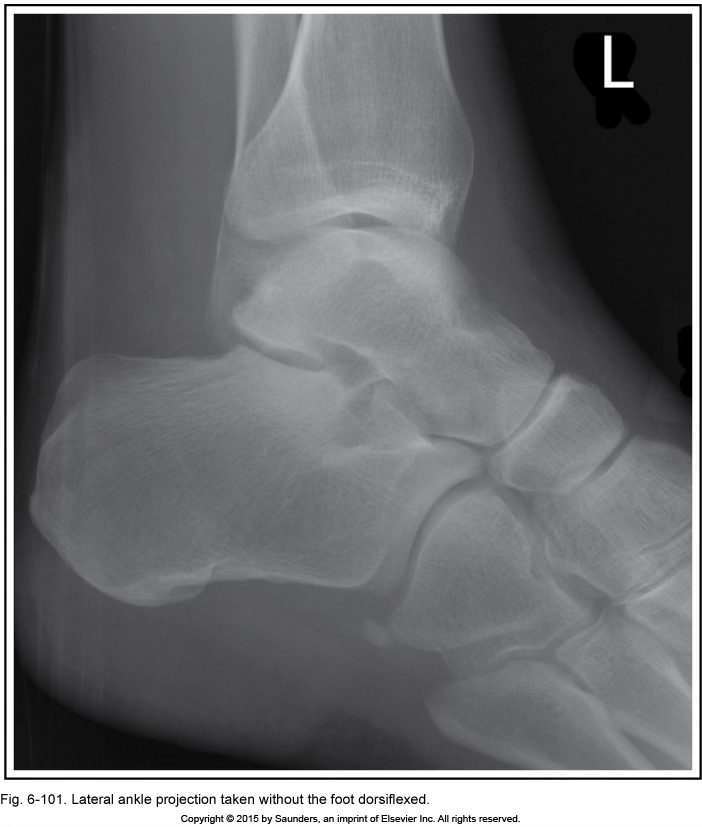

lateral ankle

foot not dorsiflexed